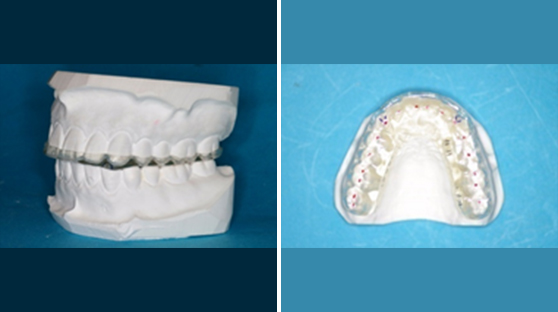

스플린트는 턱관절장애 환자의 치료를 위해 구강내에 장착하는 가철식 장치를 말합니다.

스플린트에는 여러가지 종류가 있으나, 일반적으로 재질이나 사용목적, 장치 제작시 턱의 위치를 기준으로 다음과 같이 분류합니다.

경성장치 | 연성장치 |

· 턱관절안정장치 · 전방재위치장치 · 미니 스플린트 (*가철식이 아닌 고정식으로 시술됨) | · 마우스 가드 · 임시 완충장치 |

※ 스플린트 치료는 비급여 (비보험) 항목에 해당합니다.

턱관절안정장치(Stabilization Splint, SS)는 환자가 습관적으로 입을 다무는 경로상에서 제작하는 장치로 관절 및 근육 그리고 치아와 같은 저작계 구성요소를 안정화 시키는 장치를 뜻합니다.

턱관절안정장치의 작용은 다음과 같습니다.

- 턱관절에 부가되는 과부하를 감소시킵니다.

- 치아를 보호하며, 이갈이를 감소시킵니다.

- 저작근을 이완시킵니다.

턱관절안정장치는 다음과 같은 경우에 주로 사용됩니다.

- 골관절염

- 심한 이갈이

- 만성근육장애

- 턱관절 디스크 말기

전방재위치장치(Anterior Repositioning Splint, ARS)는 전방으로 변위된 턱관절 디스크를 정상의 위치로 유도하기 위해 사용하는 장치로, 전방으로 변위된 디스크쪽으로 환자의 턱이 앞으로 이동한 상태에서 제작합니다.

전방재위치장치는 다음과 같은 경우에 사용됩니다.

- 과두걸림이나 큰 관절음을 동반한 턱관절 디스크

- 수조작으로 정복된 급성 비정복성 관절원판 전방변위 응급치료

전방재위치장치는 수면시 환자의 턱이 후방으로 이동하는 것을 막기 위해서는 상악(윗턱)에 제작하는 것이 더 유리합니다.